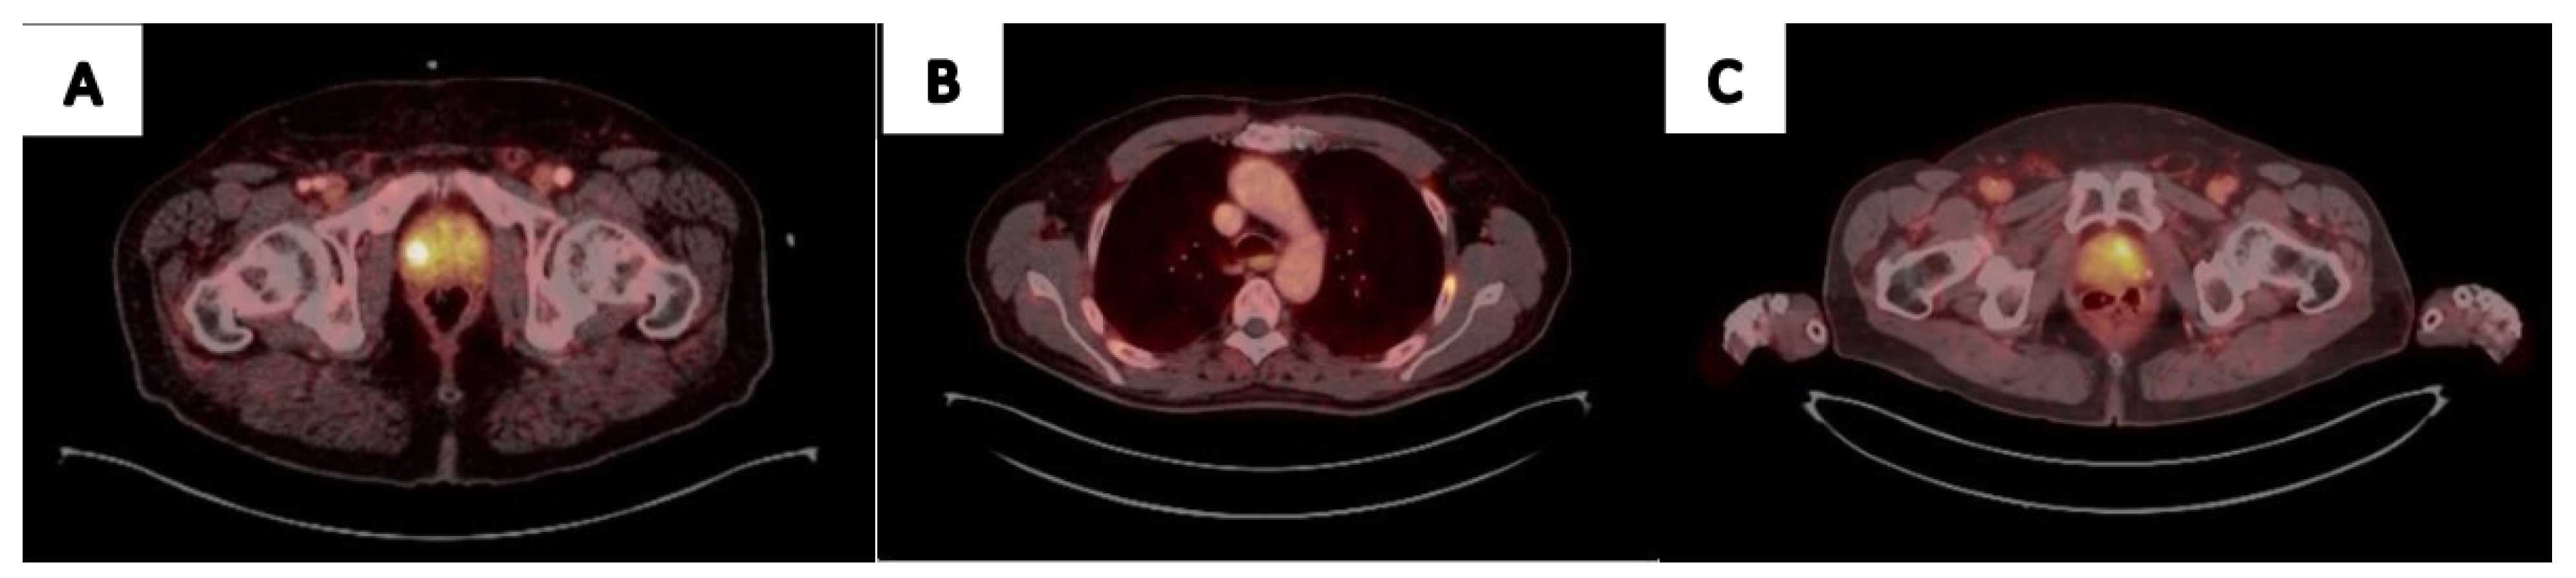

Figure 2.

68Ga-PSMA Utilization in Real-Life Prostate Cancer Management: (A) 61 yo patient, PSA-6.1mg/ml. PIRAD 3 lesion detected in MRI. 68Ga-PSMA PET CT revealed SUVmax 10.6 uptake on the Rt side. Targeted biopsy detected ISUP3 PCa. (B) 67 yo patient, was referred for surgery due to high volume ISUP2 PCa on prostate biopsy. 68Ga-PSMA PET CT uptake in the Lt rib without an apparent lesion on CT, concluded as equivocal when revised. PSA remained undetectable for 1 year following surgery. (C) 72 yo patient, PSA 1.05 mg/ml 4.5 years following external beam radiation therapy. 68Ga-PSMA PET/CT imaging revealed Lt side local recurrence. Targeted biopsy detected ISUP3 PCa.